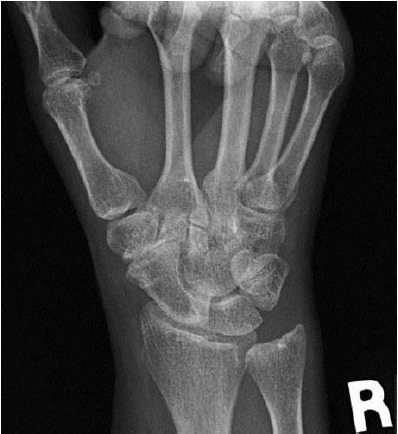

A 59-year-old woman comes for evaluation because of a 7-month history of pain over the radial aspect of the right wrist that is aggravated with forceful gripping. She denies any history of trauma to the hand or wrist. On physical examination, there is tenderness to palpation over the right anatomic snuffbox and thenar eminence. Axial load and shifting of the basal joint does not result in crepitance or pain. Resisted thumb extension at the metacarpophalangeal joint level is not painful. An x-ray study of the wrist is shown. Which of the following is the most appropriate operative management?

The correct response is Option A.

Scaphotrapeziotrapezoid (STT) arthritis can often be misdiagnosed on initial presentation as basal joint arthritis. The keys to differentiating the two sites of pain include physical examination, which shows tenderness more proximal than the basal joint and absence of pain with a grind maneuver, coupled with imaging showing osteoarthritic degeneration at the STT rather than the trapeziometacarpal level. Treatment for the arthritic pain can consist of resection arthroplasty or arthrodesis. Both techniques can provide good relief of symptoms. Resection arthroplasty often is used when the scapho-trapezoid articulation is relatively preserved. Regardless of technique chosen, the surgeon should address both the scapho-trapezial and the scapho-trapezoid joints during the procedure.

Release of the first dorsal compartment would address de Quervain tenosynovitis, which could present with pain over the anatomic snuffbox. On examination, however, the patient would typically demonstrate pain with the “resisted Hitchhiker” maneuver (resisted extensor pollicis brevis function at the metacarpophalangeal level). Given the negative findings on examination and the STT arthritis noted on imaging, this patient would not likely respond to treatment directed at the first dorsal compartment.